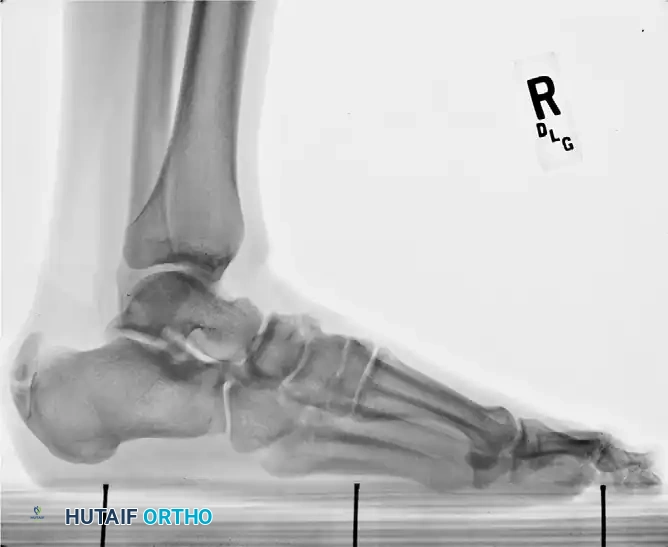

Radiographic Evaluation

Standard weight-bearing radiographs of the foot and ankle are mandatory. A standing lateral view of the heel is particularly useful for evaluating:

* The presence and size of a Haglund deformity (posterosuperior calcaneal prominence).

* Intratendinous calcific spurs extending proximally from the insertion.

* Chauveaux-Liet angle or parallel pitch lines to quantify the deformity.